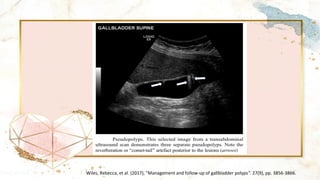

Ultrasonography

• Hyperechoic lesions protruding into the GB lumen

• Absence of post-acoustic shadow

• A fixed lesion helps to distinguish between polyps and

gallstones

• “Pseudo” polyp include a “comet tail” which arises

posterior to the lesion but not in all